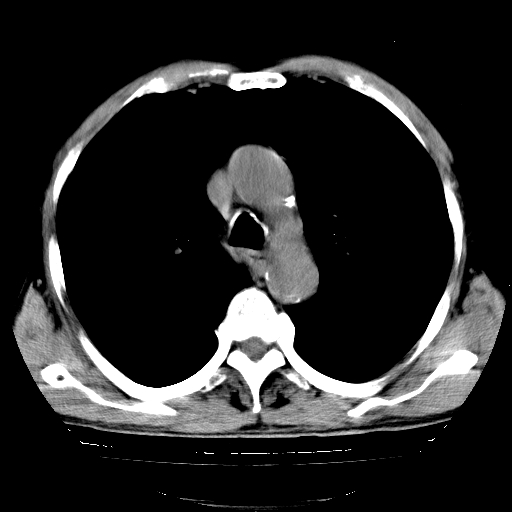

以下是引用hhcckk在2009-1-1 15:38:00的发言:[br]左下肺少许絮状模糊影--考虑感染[br]两肺散在小点状密度增高影--结合病史考虑矽肺?[br]气管壁钙化--可能由于老年退变性引起的